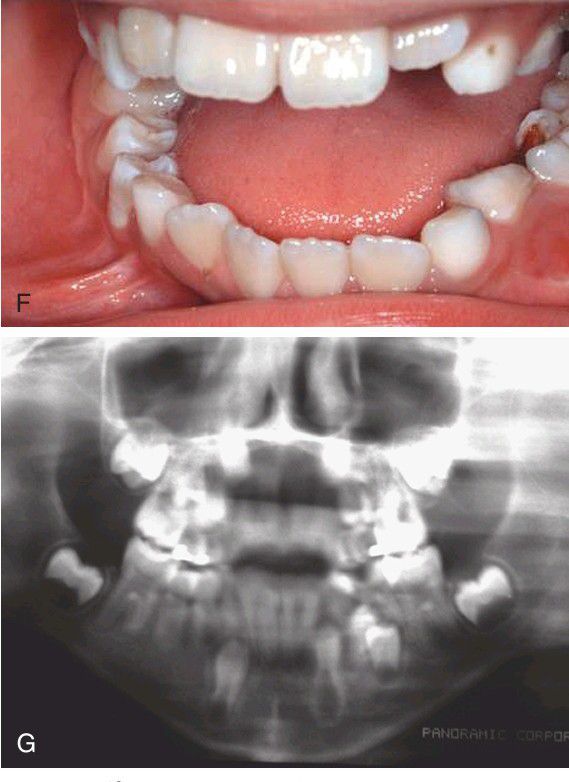

F) Clinical image taken 1 year after surgery. Both premolars have erupted. G) Panoramic radiograph taken at 1 year showing complete fill of the bone defect and eruption of the premolars